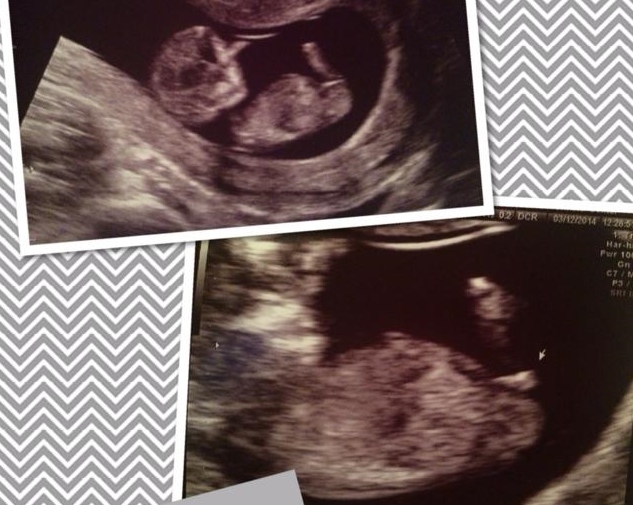

Hello! My friend sent a 12 week ultrasound pic and I was curious what you all thought! I am a complete nub amateur, just when I think I know what I'm looking at I think I'm losing my mind because women see nubs when I don't see anything...or think it's a leg.

Attachment 17522